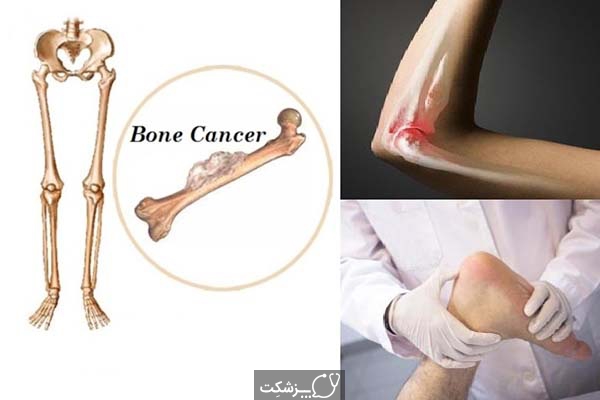

این سرطان در سنین زیر 20 سالگی رخ می دهد و احتمال ابتلاء به آن با افزایش سن کم می شود. درمان سرطان استخوان انتخاب روش درمان بستگی به نوع اندازه مرحله سرطان سن و سلامت عمومی بیمار دارد. سرطان استخوان چیست انواع سرطان استخوان. چشم انداز بهبود سرطان استخوانی بستگی به عواملی مانند سن نوع سرطان استخوان گستردگی سرطان مرحله و احتمال گسترش بیشتر آن درجه دارد به طور کلی در مورد سرطان استخوان بسیار ساده تر است که.

تشخیص سرطان استخوان. استئوسارکوم شایع ترین نوع است که بیشتر بر کودکان و نوجوانان زیر 20 سال تأثیر می گذارد. جراحی اغلب اولین انتخاب درمانی می باشد اگرچه گاهی اوقات قطع کردن عضو لازم می باشد. درمان سرطان استخوان به نوع سرطان بستگی دارد.

تومورها و کیست های سرطان دست.